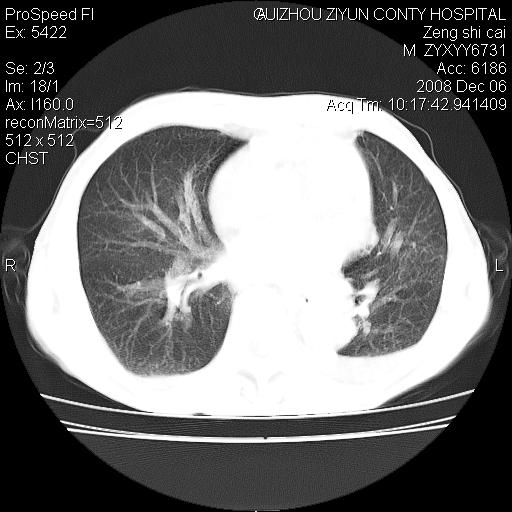

标题: CT16961:M、71岁,咳嗽半年,无血痰;胸片示右肺占位。 [打印本页]

标题: CT16961:M、71岁,咳嗽半年,无血痰;胸片示右肺占位。

右肺癌并纵隔淋巴结及胸膜转移可能性大

右肺癌并纵隔淋巴结及胸膜转移。建议气管镜

右肺纵隔型肺癌伴纵隔淋巴结及胸膜转移!

右肺纵隔型肺癌伴纵隔淋巴结转移!双侧胸水!

1)考虑右肺上叶纵隔型肺癌伴纵隔淋巴结转移。2)心包积液,双侧胸腔积液。

右肺癌并纵隔淋巴转移,腹膜后转移可能性大,两侧胸腔积液

右肺上叶纵隔型肺癌伴纵隔淋巴结转移。心包积液,双侧胸腔积液。

右上肺癌并纵隔淋巴结及胸膜转移。

右肺纵隔型肺癌伴纵隔淋巴结转移!双侧胸水\\心包积液

建议强化!主要鉴别是淋巴瘤与肺癌淋巴结转移。

右肺纵隔型肺癌伴纵隔淋巴结及胸膜转移